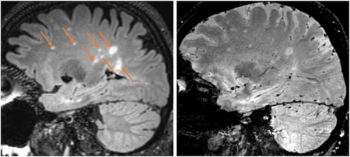

Recognition of the central vein sign with a six-minute MRI demonstrated comparable sensitivity for multiple sclerosis (MS) detection in comparison to oligoclonal band (OCB) assessment, which requires lumbar puncture, according to newly published research.